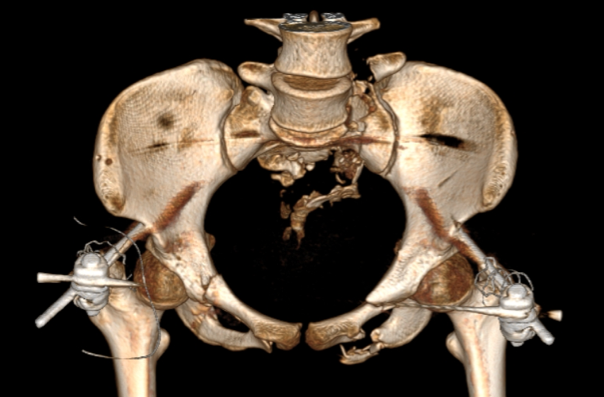

图五:术中透视验证复位结果

术中透视验证螺钉置入效果

经过2个半小时的“数智化微创手术”,患者手术切口仅有5个,切口平均长度小于1cm,术中出血量仅有50cc,“真·微创”治疗效果着实令人满意。智能化骨科手术机器人真正实现了看得见的‘快准稳’,不仅让医生有了‘超级助手’,真正意义上实现骨盆骨折微创治疗,同时对患者康复和术后生活质量极为有利。

图七:患者术后三天影像资料